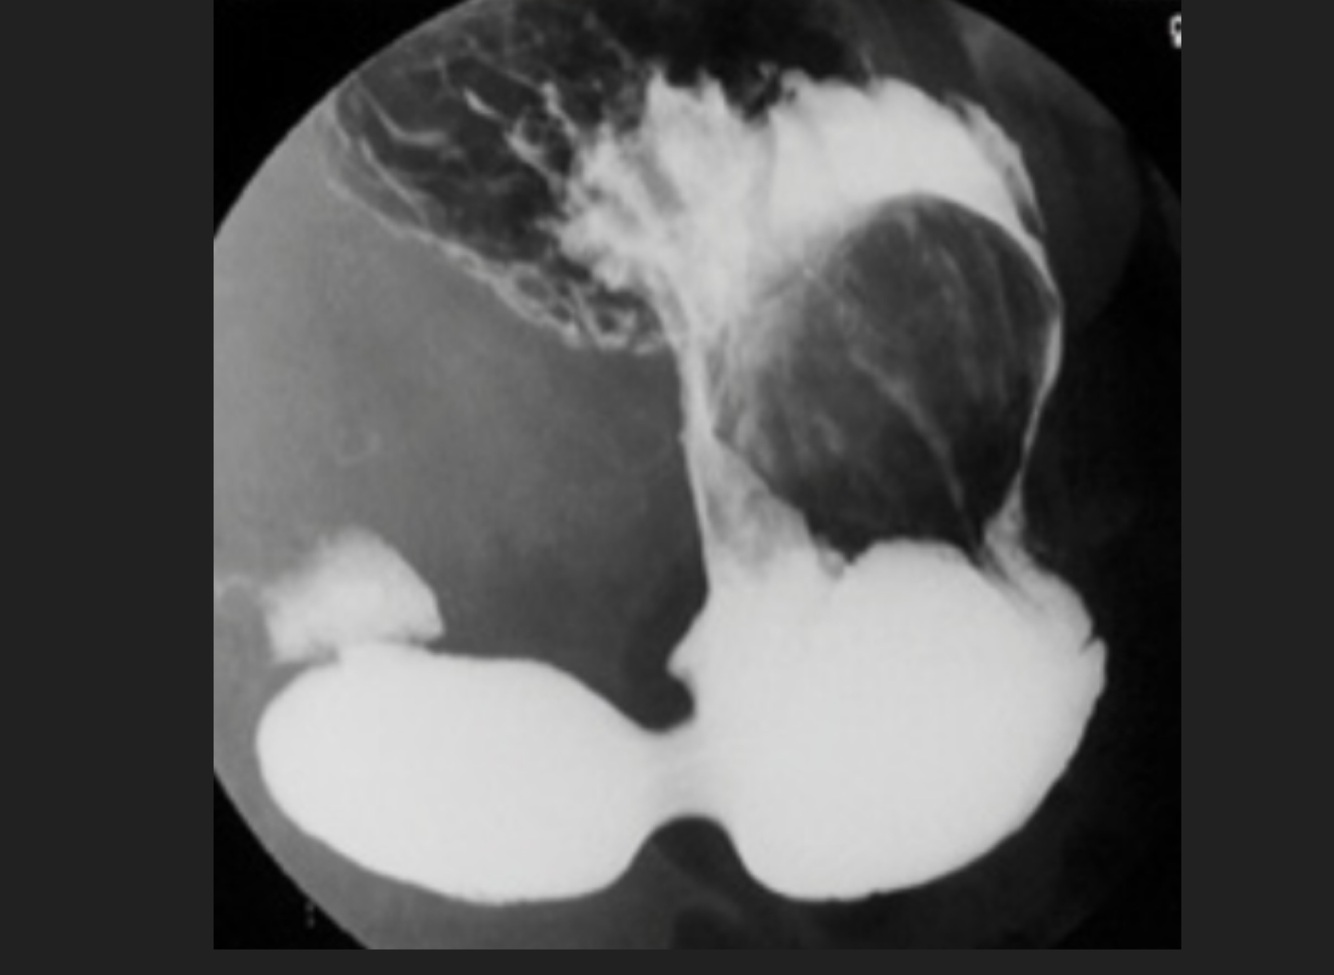

Masculino de 49 años, con IVU de repetición, Hematuria ocasional

A

Riñon en herradura